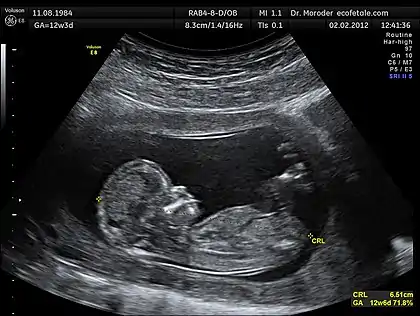

The most well know application of Biomedical Ultrasound is in medical imaging, also known as ultrasonography. For a list of specific applications of ultrasonography refer to the corresponding Wikipedia entry. The following section provides a qualitative description of the acoustical process used to generate and capture sound signals used in producing ultrasound images.

Modern ultrasonography use arrays of small transducers, each of which are individually electronically controlled to achieve an effect know as beamforming. When using this technique, control of the phase relation between array elements results in control over the emitted beam's direction and focal depth.[7] To produce a two-dimensional ultrasound image, the ultrasound beam focal position is swept through a region, and the recorded reflected waves are correlated to the particular focal locations. The exact process by which this general concept is accomplished varies with each ultrasonography instrument. Figure 1 provides a sample 2D image produced by the sweeping of the focal location through a 2D plane.